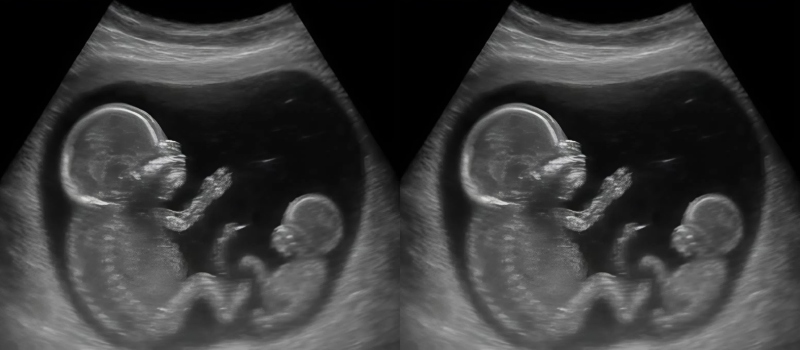

Two embryos. Two heartbeats. But developing at different stages. Weeks apart.

The doctor introduced a term they had never heard before: superfetation. A phenomenon so rare it appears only sparingly in medical literature. It refers to a second conception occurring after a pregnancy has already begun—something most experts consider extraordinarily uncommon.

As the weeks passed, reality settled in. This wasn’t just a fascinating story for friends; it required careful monitoring. One baby measured exactly where it should be, progressing steadily through the expected milestones. The other lagged slightly behind—smaller, quieter, yet undeniably present and alive.

Each ultrasound felt like watching two timelines running in parallel, slightly out of sync.